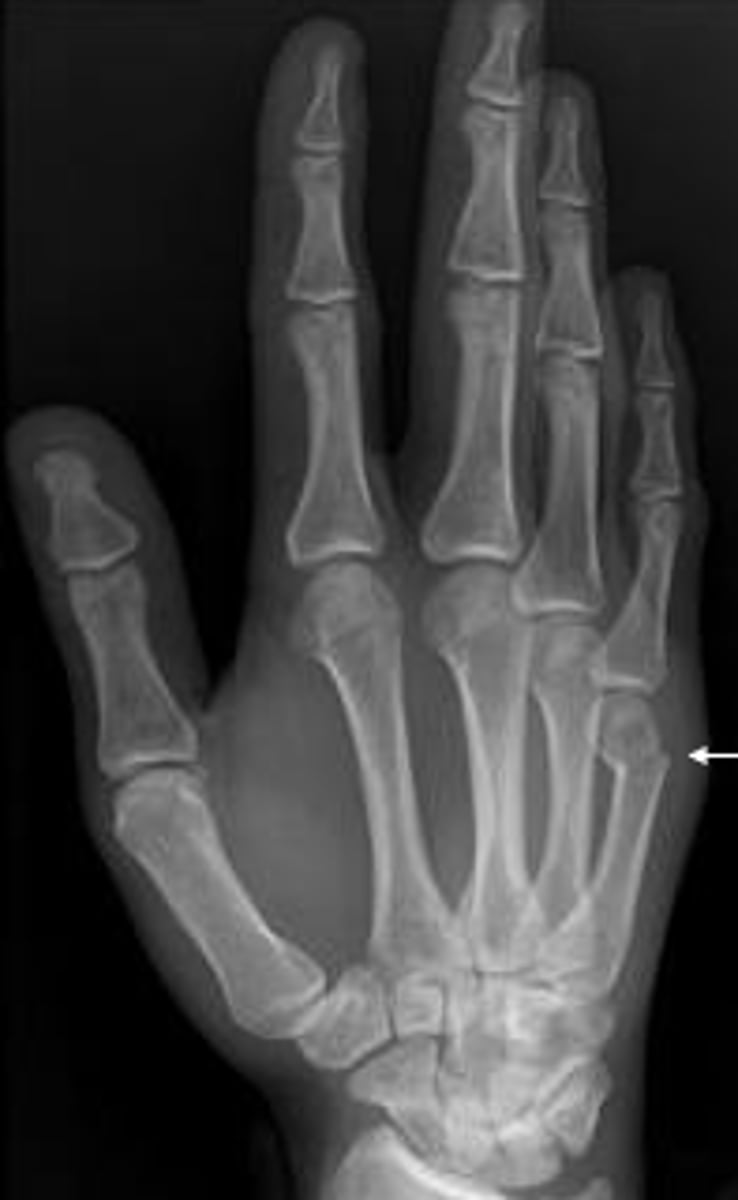

What type of fracture is this?

Answer

5th metacarpal fracture. Boxers fracture

Anything abnormal with this image of the metacarpals? 36 y/o woman

Normal metacarpals!

Note the cortex is thick and homogenous in the mid shaft of the metacarpal. it bones thinner as it approaches the ends of the bones.